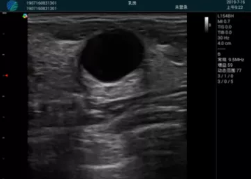

M20查看:囊內(nèi)回聲均勻,邊界清晰,囊壁光滑